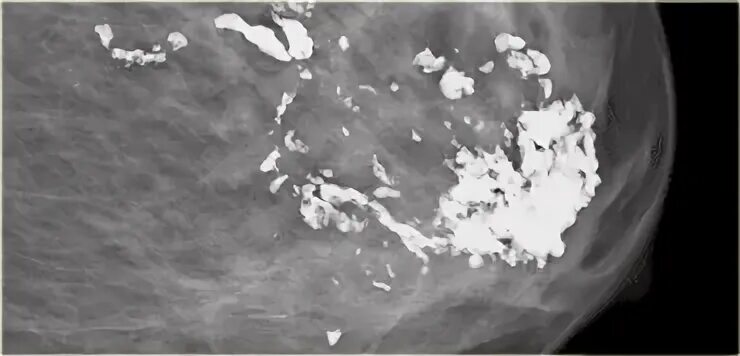

Причина образования кальцинатов